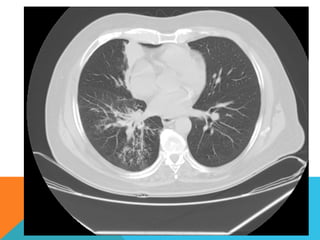

ABORDAJE TÉCNICO: Serealiza estudio con ventana mediastinal y de parénquima pulmonar con técnica de ALTA RESOLUCION, en inspiración y espiración, mediante  cortes axiales, desde ápices hasta bases pulmonares, con las siguientes observaciones En las partes blandas y las estructuras óseas dentro de los límites de la normalidad. Las regiones axilares libres. Ambos pulmones con neumatización conservada, con sobredistensión pulmonar, y áreas de atrapamiento aéreo, bilateral con cambios fibrosos cicatriciales apicales derechos. Se demuestran áreas de condensación en topografía predominantemente parenquimatosa pulmonar derecha, la mayor de ellas evidenciada hacia la base, acompañada de broncograma aéreo, la medición máxima al corte axial de 6.1 por 2.2 cm, en topografía del segmento posterior del lóbulo inferior, S10 así como también otra más se definen topografía de similares características en topografía del segmento medial del lóbulo medio, S5. En topografía parenquimatosa pulmonar izquierda imagen de similares características a las ya descritas en topografía del segmento lingular inferior, S4. No hay derrame ni áreas de engrosamiento pleurales. El patrón vascular es de características normales donde no se delimitan imágenes de lesiones aneurismáticas únicamente cambios por aortoesclerosis incipiente. El corazón de dimensiones conservada, de contornos regulares, sin desplazamientos; en la región hiliar derecha se define adenopatía de medición máxima corte axial de 1.6 por 1.4 cm.

En los cortesrealizados hacia las bases pulmonares es posible delimitar los órganos sólidos intraabdominales tales como el hígado sin anormalidades que consignar; se demuestra imagen hiperdensa puntiforme en topografía del parénquima esplénico en relación a calcificación inespecífica. Hay distensión aérea esofágica que lo define prácticamente su totalidad. Se demuestran imágenes hiperdensas en topografía intraluminal vesicular que corresponden con colelitiasis. Se define imagen hipodensa parenquimatosa renal superior derecha con patrón de atenuación homogéneo, líquido que condiciona la sospecha de lesión focal benigna tipo quística simple. INTERPRETACIÓN DIAGNÓSTICA:   ESTUDIO ANORMAL QUE DEMUESTRA HALLAZGO INESPECIFICO DE SOBREDISTENSIÓN PULMONAR  CON CAMBIOS FIBROSOS CICATRICIALES APICALES DERECHOS Y ÁREAS DE CONDENSACIÓN PARENQUIMATOSAS PULMONARES, DE PREDOMINIO DERECHO, LA DE MAYORES DIMENSIONES BASAL DERECHA, ASOCIADA CON BRONCOGRAMA AÉREO. COLELITIASIS.

El estudio radiológicosimple evidencia una lesión nodular menor del centímetro, radiodensa, caracterizada como granuloma cálcico. En mi opinión el estudio de TCAR fue realizado por ese motivo y ello permito identificar los hallazgos “floridos” que ya se señalan y se muestran en las imagen axiales ya seleccionadas.